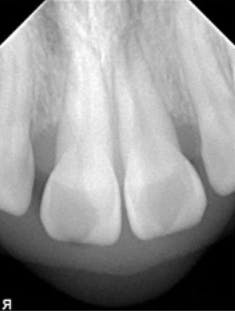

A 22-year-old female presented to a periodontal office with the chief complaint of gum swelling in the maxillary anterior (figure 2). Radiographs taken of the area showed unexpected bone loss in the maxillary central and incisor region (figure 3). The patient admitted to the dentist that she was using a technique known as gap banding that she had found out about online to close the spaces between her front teeth. She stated that she would use these bands at night while she slept, and one morning one of the bands was gone. A few months later, she developed the "swelling in her gums."